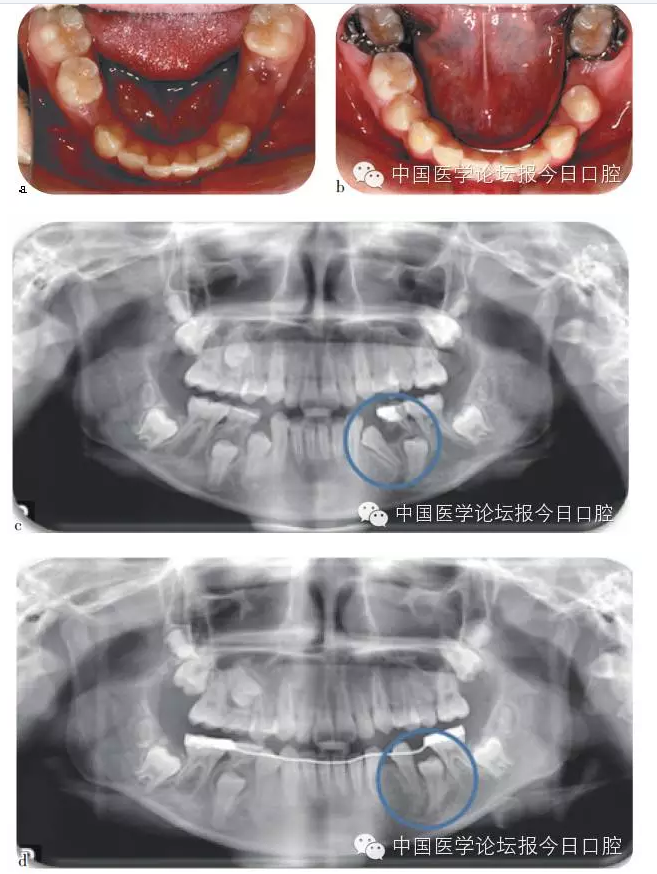

兒童齲病造成牙冠橫徑變短、乳牙早失、磨牙前移。兒童根尖周病影響恒牙發(fā)育及萌出異常、阻生。

兒童口腔疾病治療、間隙維持能預(yù)防繼承恒牙的萌出異常。

如病例一(圖1)所示,75深齲,34牙胚萌出異常,拔出75,行舌弓間隙維持后,34萌出道自行調(diào)整和萌出。

圖1 75深齲,34牙胚萌出異常,拔除75,舌弓間隙維持后,34萌出道自行調(diào)整萌出